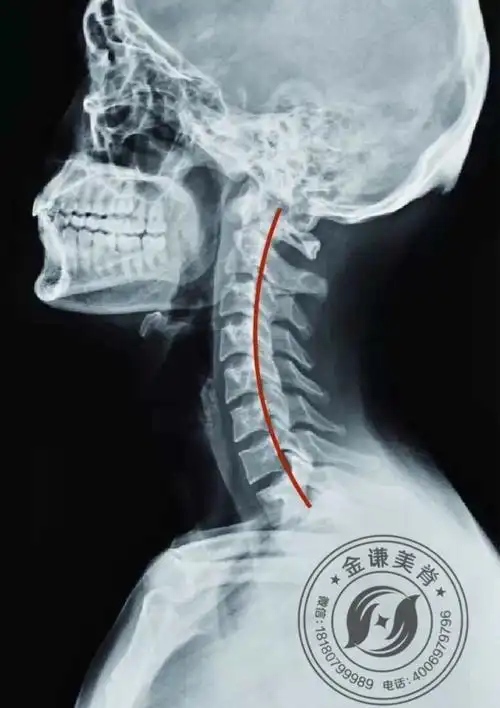

正常的颈椎会呈现c形的生理弧度,而当颈椎失去了原本的生理曲度,变得

此图为人体颈椎正常生理弧度,即c形

颈椎生理曲度是指第45颈椎向前凸出的弧度,某些原因引起弧度消失时

这个图片可以让我们认识颈椎是有生理曲度的